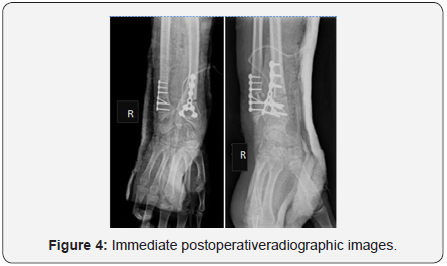

The postero anterior wrist X-rays (Figure 2) showed typical Madelung deformity changes on both wrists: shortening of the radius compared to the ulna, radially curved radius, a mismatch of the distal radioulnar joint and a triangular-shaped carpus. The lateral projection (Figure 3) demonstrated predominant changes on the right wrist: dorsal dislocation of the ulnar and an exaggerated volar tilt of the radioulnar joint in a way that made palmar carpal displacement and an anterior translation of the hand and the wrist. It was performed on the right side ametaphysic triplane osteotomy of the distal radius with Vicker’s ligament release, and an ulnar shortening osteotomy with plate fixation (Figure 4). There was no intra and postoperative complications.